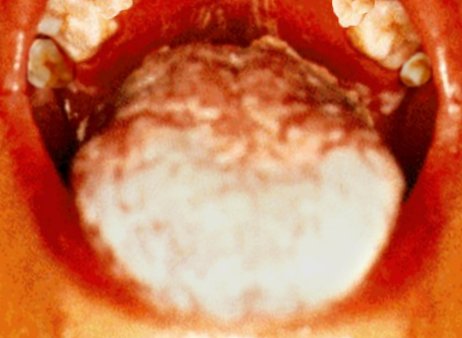

| Candidíase OralO palato do doente (acima)

e a língua (abaixo) mostram os sintomas da candidíase oral, uma infecção fúngica oportunista.